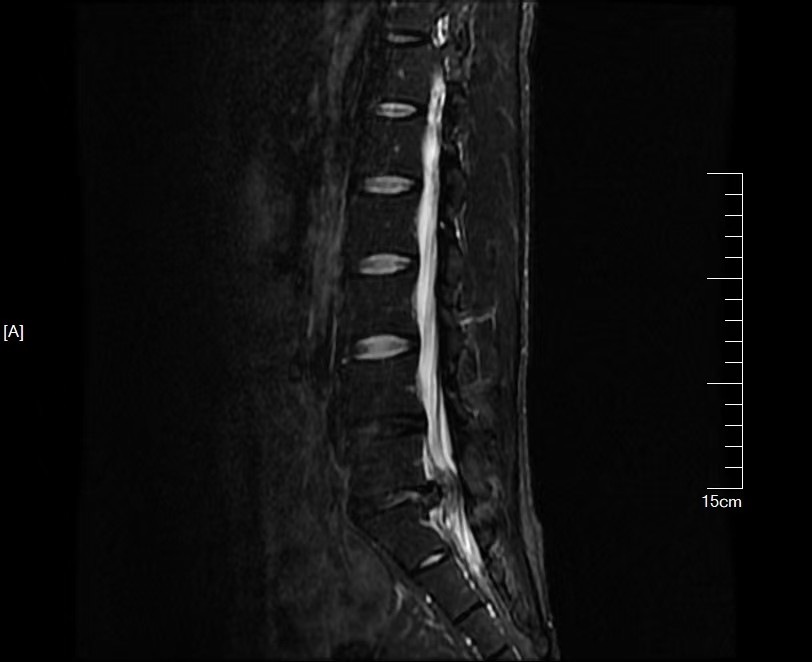

术前